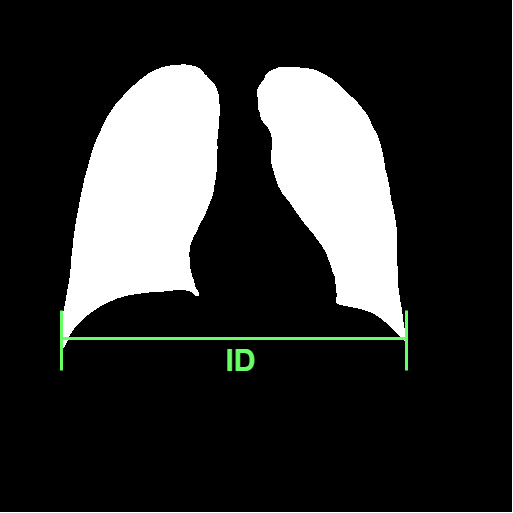

Chest radiography is the most common tool for detecting cardiomegaly due to the low cost and high availability of devices to obtain chest X-ray images. From chest X-ray images, radiologists employ CTR as one of the most important indicators of cardiomegaly due to the simplicity of the calculation. CTR of a chest X-ray image is calculated as cardiac diameter (the diameter of the heart) divided by the thoracic diameter (the diameter of the chest). Specifically, CTR can be calculated from three measurements, , the midline-to-right heart diameter, , the midline-to-left heart diameter, and , the internal diameter of chest [2, 3], as

| (1) |

where and is measured from the greatest perpendicular diameter from midline to right and left heart border, respectively. Figure 1 visualizes the details of CTR calculation. A CTR value of is generally considered to indicate the upper limit of normal.